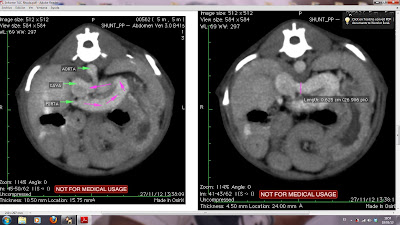

Se trata de un perro de 5 meses de raza terrier que es dignosticado de un shunt portosistemico por la sintomatologia y resultados de laboratorio. Para confirmar las sospechas, y aqui viene la novedad, realizan una tomografia computerizada para valorar la vasculrizacion abdominal y confirmar la existencia del vaso anormal.

Vemos una comunicacion portocavade mas de 6 mm de diametro que aparece de manera sinuosa de derecha a izquierda justo craneal a la arteria renal y la frenicoabdominal.